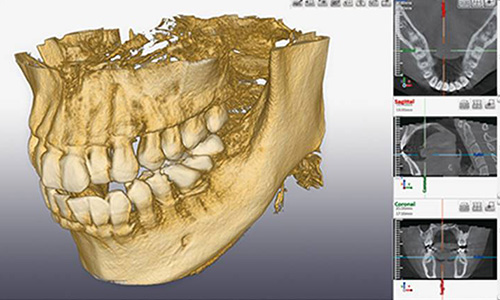

歯科用CT

CTとは、コンピュータ断層撮影(Computed Tomography)の略称で、コンピュータ処理により撮影データを3次元の立体画像として構築することで、骨の状態などを正確・高精度に診断できる装置のことをいいます。

従来のレントゲン画像は、2次元の平面画像でしか歯や顎の骨の様子を見ることが出来ませんでしたが、歯科用CTを用いることで、3次元の立体画像として情報を得ることが出来るため、歯や顎の骨の状態はもちろんのこと、神経や血管の位置なども詳細に把握するできるようになります。

当院では主に、親知らずの抜歯やインプラント、歯周病治療、根管治療、歯根の破折の診断などに用いています。